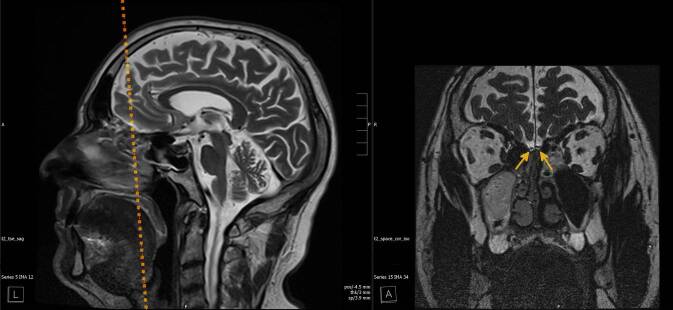

嗅觉障碍是耳鼻喉科评估的常见原因。特别是当主观和/或客观嗅觉测量的结果不确定时,需要额外的客观发现来验证嗅觉障碍。根据实际经验,并考虑到目前的文献,这篇文章的目的是作为辅助准备补充放射学报告。除了详细的病史和既往发现(如果适用)外,还应强调综合最新标准影像学的重要性,包括嗅球体积测定。除了与嗅觉有关的解剖结构的改变的文献,这支持了报道的嗅觉障碍,特殊的嗅球可视化神经放射学检查序列,包括体积测量,可以为评估有时仅主观存在的嗅觉障碍提供客观成分。在大多数情况下,没有有效的比较体积可以从可能预先存在的影像学研究中得出。因此,与嗅球参考值进行比较,在研究中确定了假定的病因和由嗅测法报告/确定的疾病程度,这是将嗅球体积与报告和/或由嗅测法确定的嗅觉功能保持几乎客观关系的唯一方法。

Disorders of olfaction are a frequent reason for an assessment in otorhinolaryngology. Particularly when the results of subjective and/or objective olfactometry are inconclusive, additional objective findings are required to verify disorders of the sense of smell. Based on practical experience and considering the current literature, this article is intended as an aid in the preparation of supplementary radiological reports. The importance of comprehensive up to date standard imaging including olfactory bulb volumetry in addition to a detailed medical history and, if applicable, previous findings should be emphasized. In addition to the documentation of alterations in the anatomical structures involved in olfaction, which support the reported disorders in the sense of smell, special neuroradiological examination sequences for the visualization of the olfactory bulb, including a volumetric measurement of the same, can provide an objective component for the assessment of sometimes only subjectively existing disorders of the sense of smell. In the majority of cases no valid comparative volumetry can be derived from a possibly pre-existing imaging study. Therefore, a comparison with olfactory bulb reference values, determined in studies for the presumed etiology and the extent of the disorder reported/determined by olfactometry is the only way to put the olfactory bulb volume in an almost objective relationship to the function of the sense of smell reported and/or determined by olfactometry.